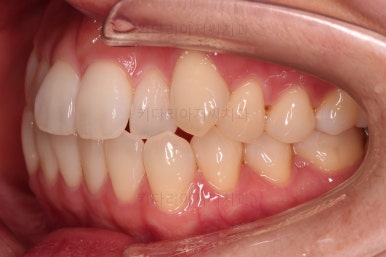

삐뚤한 덧니를 가지런하게 하기 위해서 필요한 부분의 어금니를 순차적으로 뒤로 밀어줍니다.

자세히 보면 치아 사이사이에 틈새가 생기는게 보이죠?

틈새를 일부러 만들어 해당 공간으로 덧니를 가지런하게 하는 원리입니다.

장치를 사용한지 1년 2개월째 사진입니다.

매우 가지런해졌죠.